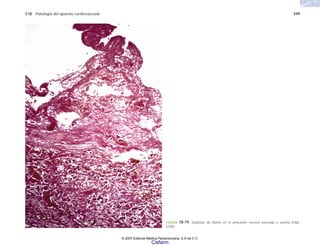

presión arterial